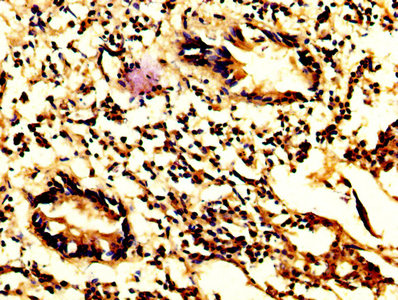

IHC image of CSB-PA15479A0Rb diluted at 1:200 and staining in paraffin-embedded human ovarian cancer performed on a Leica BondTM system. After dewaxing and hydration, antigen retrieval was mediated by high pressure in a citrate buffer (pH 6.0). Section was blocked with 10% normal goat serum 30min at RT. Then primary antibody (1% BSA) was incubated at 4°C overnight. The primary is detected by a biotinylated secondary antibody and visualized using an HRP conjugated SP system.